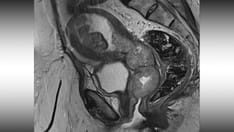

CT scan of cervical cell carcinoma demonstrates markedly enlarged lymph node at left pelvic sidewall. This is consistent with pelvic lymph node metastasis, which is indicative of stage IIIB disease. Cystic consistency is not unusual for metastatic cervical carcinoma. Primary tumor is well depicted as hypoattenuating circumscribed mass. Cyst is present in anteriorly located left ovary.